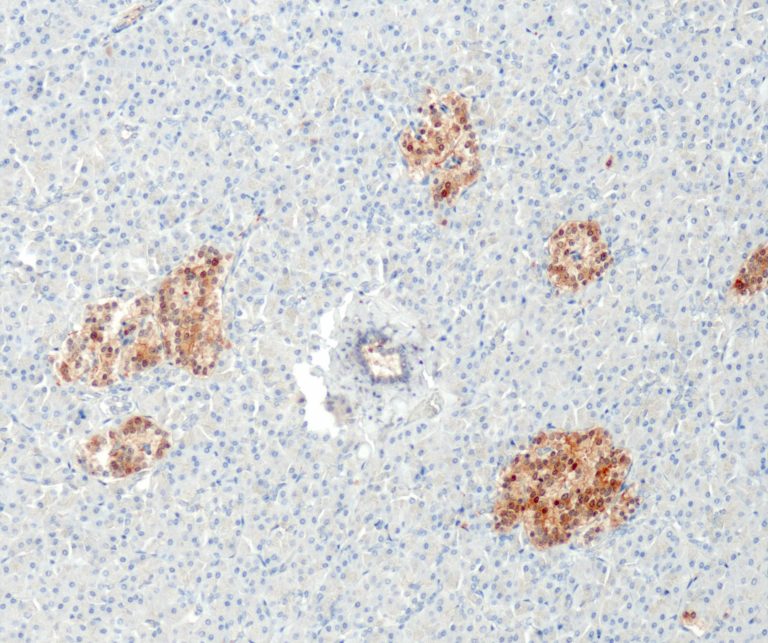

Endocrine Pathology